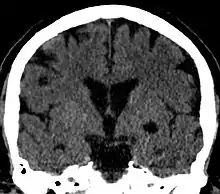

Coronal CT of the brain showing a choroidal fissure cyst

A choroidal fissure cyst is a cyst at the level of the choroidal fissure of the brain. They are usually asymptomatic and do not require treatment.